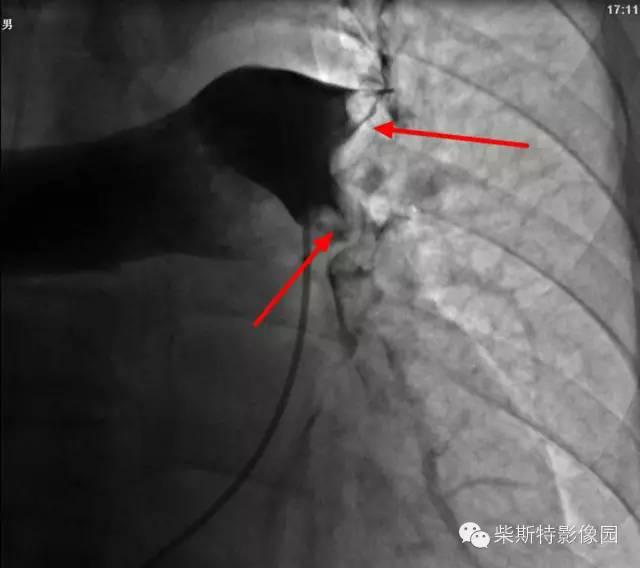

第一大名捕:肺动脉造影

红色箭头所指处即为栓子导致的充盈缺损。尽管肺动脉造影目前已经被肺动脉CTA所替代,但是其“老大”的地位还是无法撼动!

“老大”的绝招是其不仅可以提供整体的肺血管的解剖学资料,而且可以提供血流动力学参数,即可以用于诊断也可以用于治疗,如急性肺栓塞的导管内局部溶栓、捣栓、碎栓、抽栓,先天性肺动脉狭窄的球囊扩张、支架植入、肺动静脉瘘的栓塞治疗等。